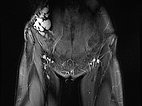

Koronare, T2-gewichtete, fettunterdrückte MRT des Unterbauchs auf Höhe der Leisten. Unauffällige Leistenlymphknoten. Die lymphatische Malformation der Bauchwand stellt sich in großen, dysplastischen, ballonartigen, gekammerten Zysten dar, die stark hyperintens (weiß) sind.

Gleiche Schnittführung in der nativen T1-Wichtung (MRT). Die Zysten der lymphatischen Malformation sind isointens zur Muskulatur. Damit keine lokale Einblutung.